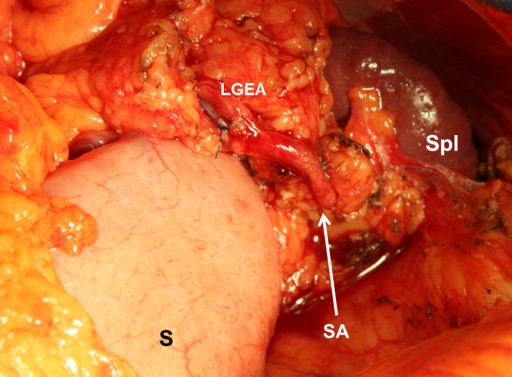

Given that the left gastroepiploic artery is not easily identifiable either intraoperatively (Figure 10) or on section [32], and is usually conserved in a spleen-preserving distal pancreatectomy with resection of the splenic vessels, this alone makes it unreasonable to credit the short gastric arteries with being the primary spleen-supplying collaterals. Anticipating that the short gastric arteries should be the primary spleen-supplying collaterals is, to a large degree, intrinsically conceptual since none of the studies has shown the direction of the blood flow in these vessels following splenic artery resection. We were prompted into carrying out our investigation by the supposition that such a large parenchymal organ as the spleen could be amply supplied with blood through collaterals less than 1 mm in diameter.

Figure 10. View of the operating field after a spleen-sparing distal pancreatectomy with resection of the splenic vessels. The left gastroepiploic artery is of the same diameter as the terminal portion of the splenic artery (arrow). LGEA: left gastroepiploic artery; S: stomach; SA: splenic artery’s terminal portion; Spl: spleen |